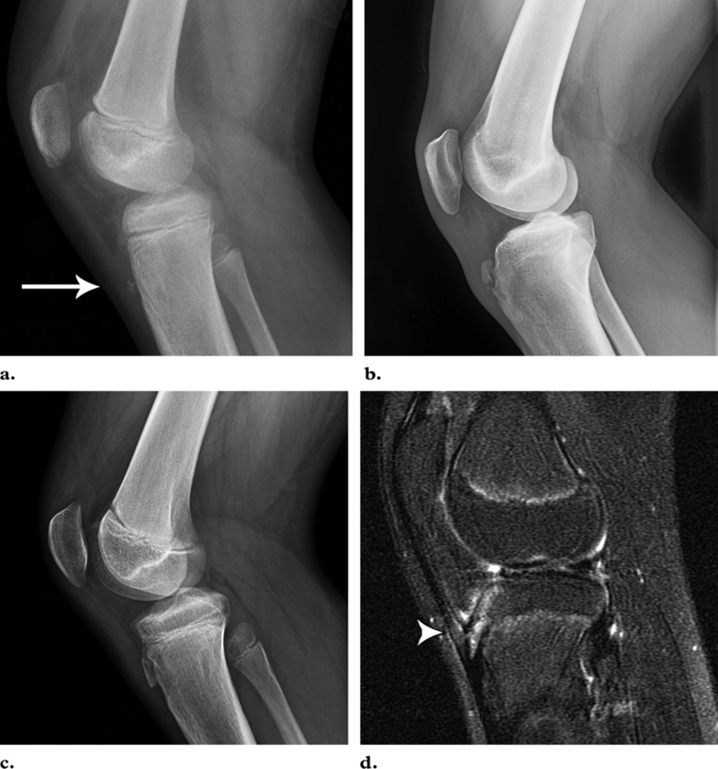

Болезнь Осгуд-Шлаттера: возможности визуальной диагностики

Остеохондропатия. Осгуда - Шлаттера болезнь. + | Портал радиологов